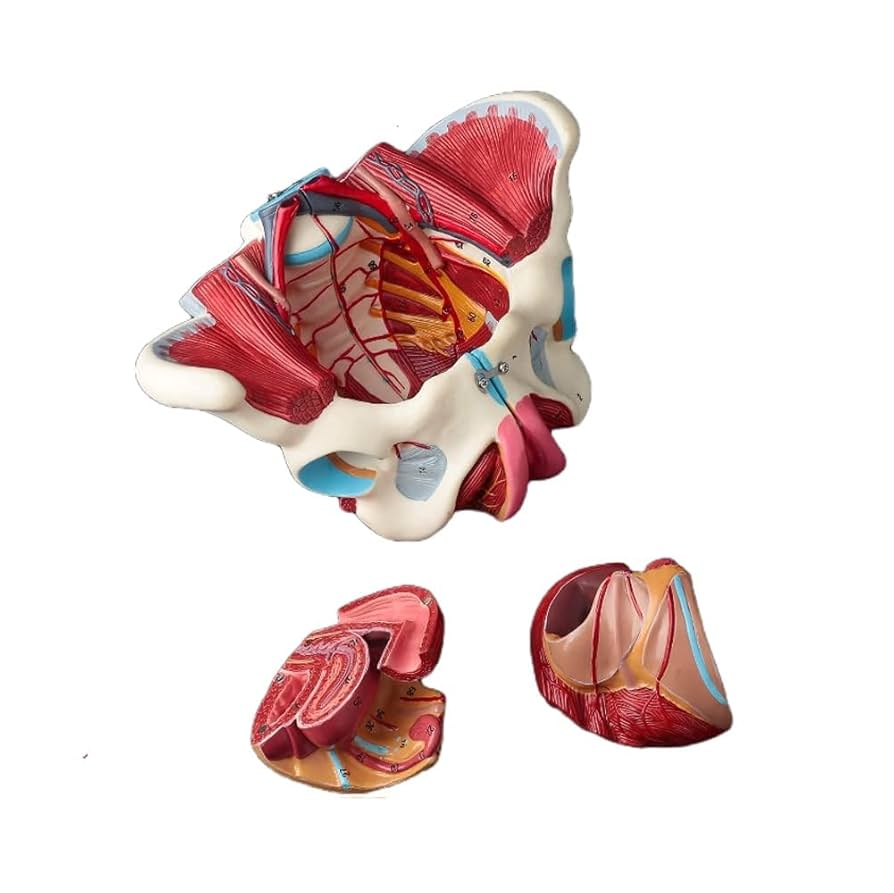

KIYOMARU 骨盤底筋付き女性骨盤模型 人体模型 8パーツ KIYOMARU 骨盤底筋付き女性骨盤模型 人体模型 8パーツ - メルカリの詳細情報

KIYOMARU 骨盤底筋付き女性骨盤模型 人体模型 8パーツ - メルカリ。Amazon.co.jp: 人体モデル 女性骨盤モデル 骨盤底筋ベル 1:1。Amazon.co.jp: 骨盤靭帯や骨盤底筋,骨盤内臓,血管や神経なども。【新品・未開封品】【即日発送】『KIYOMARU 骨盤底筋付き女性骨盤模型 人体模型 8パーツ 理学療法士監修 生殖器 膀胱 直腸 坐骨神経・陰部神経 日本語説明書付き 』参考価格:13980円 ✅解剖の理解や臨床のサポート:骨盤底筋や一部の神経(坐骨神経、陰部神経)、生殖器や排泄器が再現されており、解剖の理解や臨床をサポートしてくれます(日本語説明書付き)✅分解&組立可能:骨盤本体(骨盤底筋、一部の神経付き)、膀胱、子宮、直腸、会陰部、仙結節靭帯にて分解可能。✅サイズ(土台あり):幅26cm×奥行17cm×高さ24cm (骨盤腔の直径 左右約11.5cm 前後11cm) 重量 約1400g 原産国:中国。Amazon.co.jp: 人体モデル 女性骨盤モデル 骨盤底筋ベル 1:1。説明・セミナー・実技トレーニングなど幅広い用途でご使用いただけます✅各分野の教材として:産婦人科・泌尿器科・整形外科・リハビリ・ヨガ・整体など各方面にて説明や学習の理解の促進に。可動式脊椎模型 約90cm 椎間板突出(ヘルニア)モデル スタンド付き